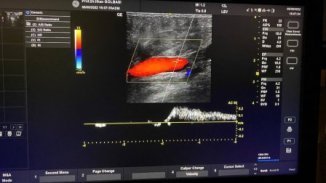

Video. Dopplerde ultrasonda toplardamar kaçağının gösterilmesi

Doppler ultrasonda akım grafiğinde normal akımı cizgi üstündeki trase temsil etmekte. Hastanın ıkınma hareketi ile birlikte kapakçıklar kapanmakta ve geri kaçırmaya başlamaktadır ve cizgi altındaki traseyi oluşturmaktadır.

Ayrıca kaçak akım Doppler ultrasonda görüntülenebilmektedir. Burda normal akım mavi renkli iken geriye olan kaçak akım renk değiştirerek kırmızıya dönüşür.